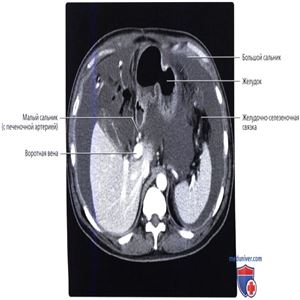

Сальниковая сумка и брюшинная полость расширены асцитической жидкостью. Желудочно-селезеночная связка и поджелудочная железа образуют границу сальниковой сумки, как и малый сальник, положение которого обозначается воротной веной и чревным стволом.

Малый сальник и желудочно-селезеночная связка образуют две из стенок сальниковой сумки. Малый сальник на этом изображении можно идентифицировать по расположению воротной вены и печеночной артерии.